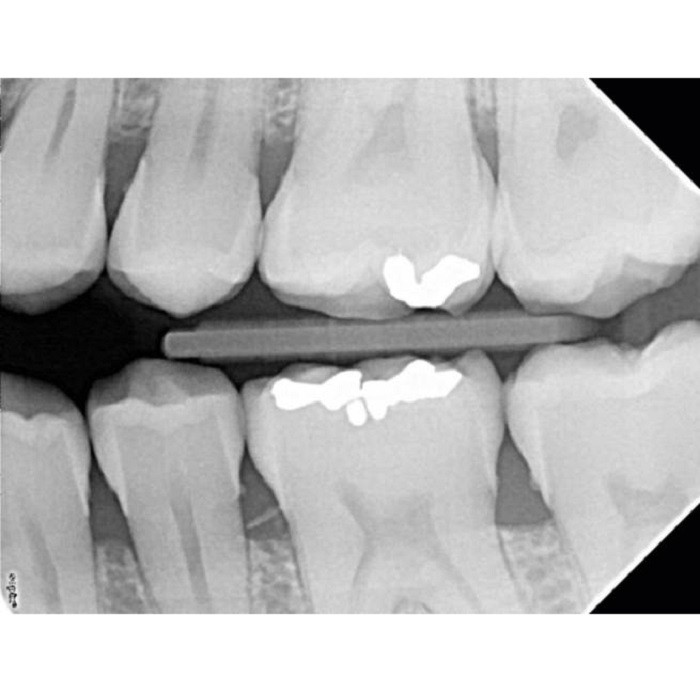

Satelec X-Mind DC Mobile - высокочастотный мобильный дентальный рентгеновский аппарат (Франция)

Satelec X-Mind DC Mobile: Мобильный рентген для современной стоматологии

Высокочастотный ментальный рентгеновский аппарат Satelec X-Mind DC Mobile — это воплощение французского качества и инноваций в компактном и автономном формате. Разработанный для клиник, где важны мобильность, скорость работы и бескомпромиссное качество снимков, этот аппарат становится надежным партнером в ежедневной диагностической практике.

- Высокочастотная технология: Использование высокочастотного генератора обеспечивает стабильное и высокое качество рентгеновского изображения при минимальной дозе облучения для пациента и персонала. Это соответствует современным стандартам безопасности.

- Совместимость с цифровыми технологиями: Аппарат идеально подходит для работы с цифровыми радиовизиографными датчиками и PSP-системами (фосфорными пластинами), что позволяет сразу интегрировать его в цифровой рабочий поток клиники.